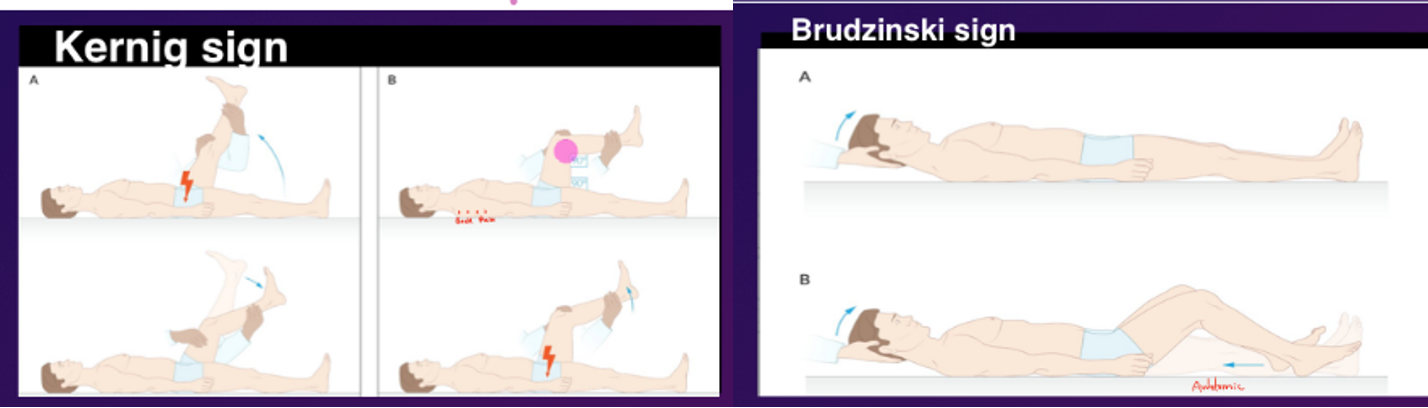

20-year-old male. Severe headache, neck stiffness, photophobia & fever X 1 day. On examination, pain on extending the leg, as shown below:

20-year-old male. Severe headache, neck stiffness, photophobia & fever X 1 day. On examination, pain on extending the leg, as shown below:

Q1: What’s the clinical diagnosis? Meningitis

Q2: Name the 2 most common etiologic agents in this age group (names of bacteria)? Pneumococci, Meningococci

Q3: Which medicine will you give you close contacts of this pt for prophylaxis? Rifampicin | Ceftriaxone in pregnant